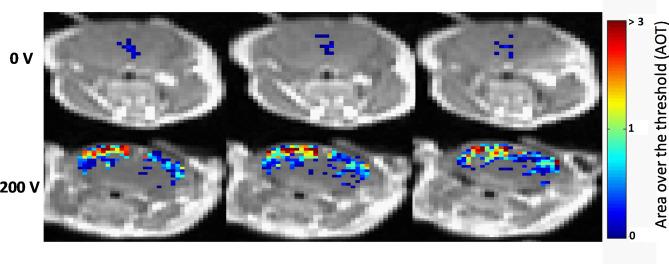

L-PEFs were applied using plate electrodes placed on the intact skull of naïve mice. L-PEFs/Sham mice were scanned immediately after the procedure by DCM ("MRI experiment"), or injected with Doxo and Trypan blue followed by delayed (4 h) perfusion and brain extraction ("Doxo experiment"). Doxo concentrations were measured in brain samples using confocal microscopy and compared to IC of Doxo in glioma cell lines in vitro. In order to map BBBo extent throughout the brain, pixel by pixel MR image analysis was performed using the DCM data. Finally, the efficacy of L-PEFs in combination with Doxo was tested in nude mice bearing intracranial human glioma tumors.

Significant amount of Doxo was found in cortical regions of all L-PEFs-treated mice brains (0.50 ± 0.06 µg Doxo/gr brain) while in Sham brains, Doxo concentrations were below or on the verge of detection limit (0.03 ± 0.02 µg Doxo/gr brain). This concentration was x97 higher than IC of Doxo calculated in gl261 mouse glioma cells and x8 higher than IC of Doxo calculated in U87 human glioma cells. DCM analysis revealed significant BBBo levels in the cortical regions of L-PEFs-treated mice; the average volume of BBBo in the L-PEFs-treated mice was x29 higher than in the Sham group. The calculated BBBo levels dropped exponentially as a function of BBBo threshold, similarly to the electric fields distribution in the brain. Finally, combining non-invasive L-PEFs with Doxo significantly decreased brain tumors growth rates in nude mice.

在所有接受 L-PEF 治疗的小鼠大脑的皮质区域都发现了大量的 Doxo(0.50 ± 0.06μg Doxo/gr 脑),而在 Sham 大脑中,Doxo 浓度低于或接近检测限(0.03 ± 0.02μg Doxo/gr 脑)。这一浓度是在 Gl261 小鼠神经胶质瘤细胞中计算出的 Doxo 的 IC 的 x97 倍,是在 U87 人神经胶质瘤细胞中计算出的 Doxo 的 IC 的 x8 倍。DCM 分析显示,在接受 L-PEF 治疗的小鼠皮质区域存在显著的 BBBo 水平;接受 L-PEF 治疗的小鼠的平均 BBBo 体积比 Sham 组高 x29。计算出的 BBBo 水平随着 BBBo 阈值的指数下降,类似于大脑中电场的分布。最后,将非侵入性的 L-PEF 与 Doxo 联合使用,显著降低了裸鼠脑肿瘤的生长速度。